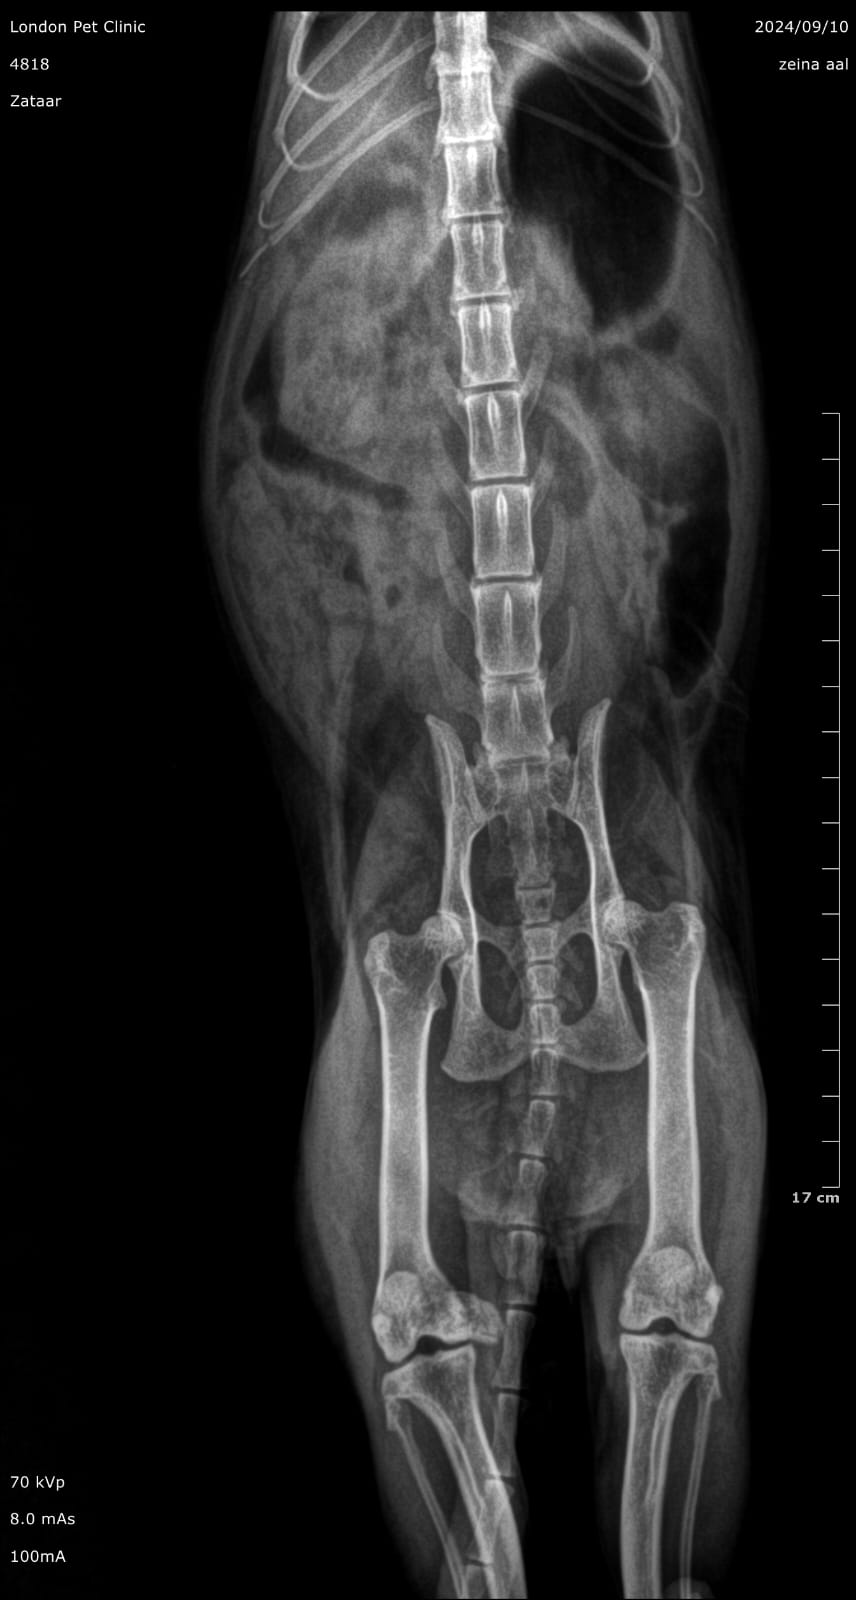

Abdominal radiographs: May show a gas--distended stomach with clogging clump

Abdominal ultrasound: was consistent of GOO due to hairball with fluid accumulation in the stomach

Post-Operative X ray